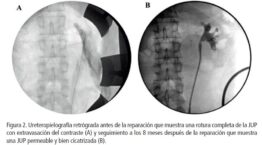

Esto sugirió la ruptura completa de la juntura ureteropiélica ( JUP), que se confirmó en la ureteropielografía retrograda (fig. 2A) y enrollamiento del stent ureteral fuera de la pelvis renal.

El paciente fue sometido a laparotomía para el manejo de lesiones concomitantes y se tomó la decisión de una reparación quirúrgica temprana de la ruptura de la JUP mediante una técnica de anastomosis en paracaídas termino terminal con colocación de stent ureteral. La pielografía retrógrada de seguimiento y la exploración de función renal a los 8 meses mostraron la JUP bien cicatrizada (fig. 2B) y función renal diferencial del 35% para el riñón lesionado. El nivel de creatinina a los 3 años después de la lesión fue de 1,1 mg /dl.